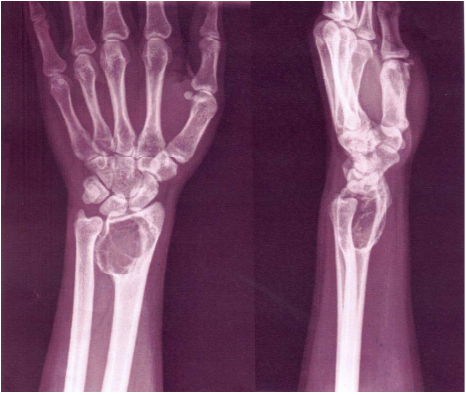

72 30 歲女性病患,外傷後手腕疼痛,最初先採民俗療法,一個半月後未見改善,故接受影像檢查。A 圖為正面之 X 光攝影,B 圖為 T1WI, coronal view,病患正確診斷應為何?

(A)osteomyelitis of scaphoid (B)scaphoid fracture with avascular necrosis (C)lunate fracture with dislocation (D)osteolytic bone tumor of scaphoid with fracture